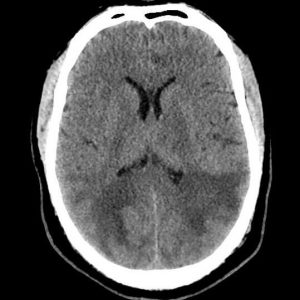

Xuất huyết não